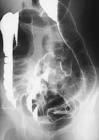

There is complete loss of haustral markings in the diseased section of colon, and the organ appears smooth-walled and cylindrical. The lead pipe appearance of colon is the classical barium enema finding in chronic ulcerative colitis. Learning Radiology - Ulcerative Colitis Ulcerative Colitis: Barium enema examination demonstrates loss of haustral folds in the entire descending colon with small ulcerations suggested. A middle-aged female with inflammatory bowel disease (IBD) (with mixed features of ulcerative colitis and Crohn s disease iron deficiency anaemia and recurrent Clostridium difficile colitis presented to the emergency department with complaints of abdominal pain, haematochezia and diarrhoea). One effect of lead pipe colon is that there is less surface area available to absorb water, which can lead to diarrhea and subsequently, dehydration.